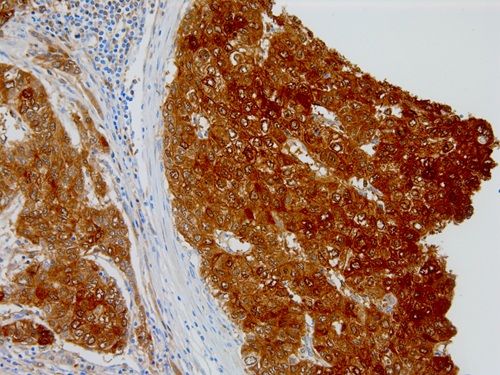

Immunohistochemical staining of human hepatocellular carcinoma tissue sections using LFABP Mouse Monoclonal Antibody (ARM629).